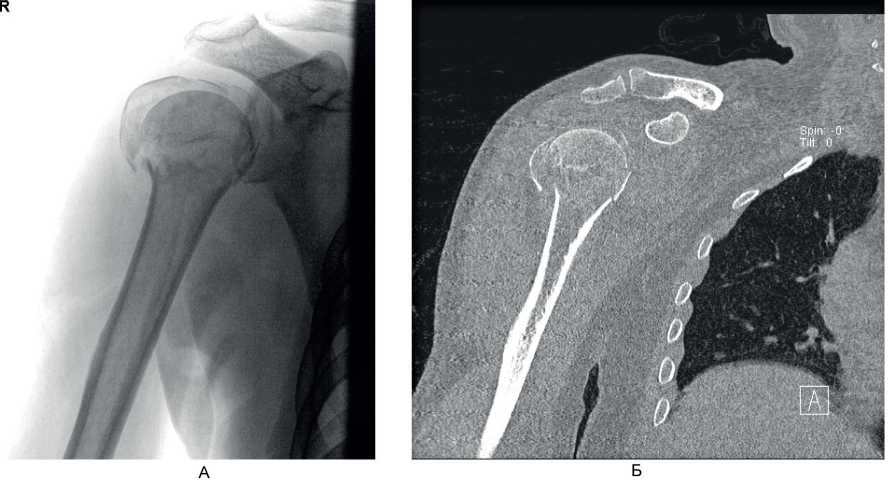

Клинический пример 2. Больной А., 50 лет, поступил в клинику ВЦЭРМ им. А.М. Никифорова в экстренном порядке. Выполнены рентгенография плечевого сустава в стандартных проекциях (рис. 8А), и компьютерная томография (см. рис. 8Б).

Рис. 8. Больной А., 50 лет. А – рентгенография плечевого сустава в стандартных проекциях; Б – компьютерная томография до операции

Перелом по классификации АО – С3.1. На 2-е сутки после поступления выполнено оперативное вмешательство – БИОС хирургической шейки правой плечевой кости. Рентгенография на 1-е сутки после операции представлена на рис. 9А, Б, контрольная рентгенография плечевого сустава через 6 мес после операции – на рис. 9В. Функциональный результат после операции – на рис. 10.

Рис. 9. Больной А., 50 лет. А, Б – рентгенография на 1-е сутки после операции; В – через 6 мес после операции